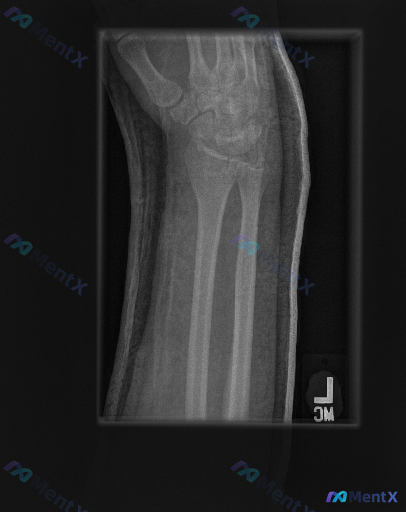

大家好,今天我们来讨论一份左侧腕部外伤后的X光片资料。先给大家看一下三个体位的影像学观察结果: 1. 放射影像-手腕处X光片-正位 (AP View) 骨骼完整性: 桡骨远端: 桡骨远端干骺端见明显骨折线,皮质连续性中断,呈现典型的背侧移位(Colles骨折特征),伴有明显的背侧成角和嵌插表现。桡骨...

整理到一份左前臂及腕部侧位X光片的影像资料,先和大家同步客观所见的线索: 1. 骨骼方面:桡骨远端背侧和掌侧皮质有连续性中断,可见骨折线涉及关节面,断端有背侧移位、背侧成角的表现,局部有粉碎或压缩改变;尺骨远端(尺骨茎突)处也可见透亮线。 2. 关节方面:桡腕关节的对应关系有改变,随桡骨移位出现背侧...

整理到一张左手腕及前臂正位X光片及配套的影像学观察内容,先把客观表现列出来,大家一起读片讨论: 影像客观表现 - 骨骼:桡骨远端可见骨质断裂线,涉及关节面,骨折端有移位和粉碎表现,骨皮质连续性中断,断端有台阶样改变;尺骨茎突也可见骨质断裂线,呈撕脱性表现;舟骨、月骨等腕骨形态大致正常;桡尺骨干皮质连...